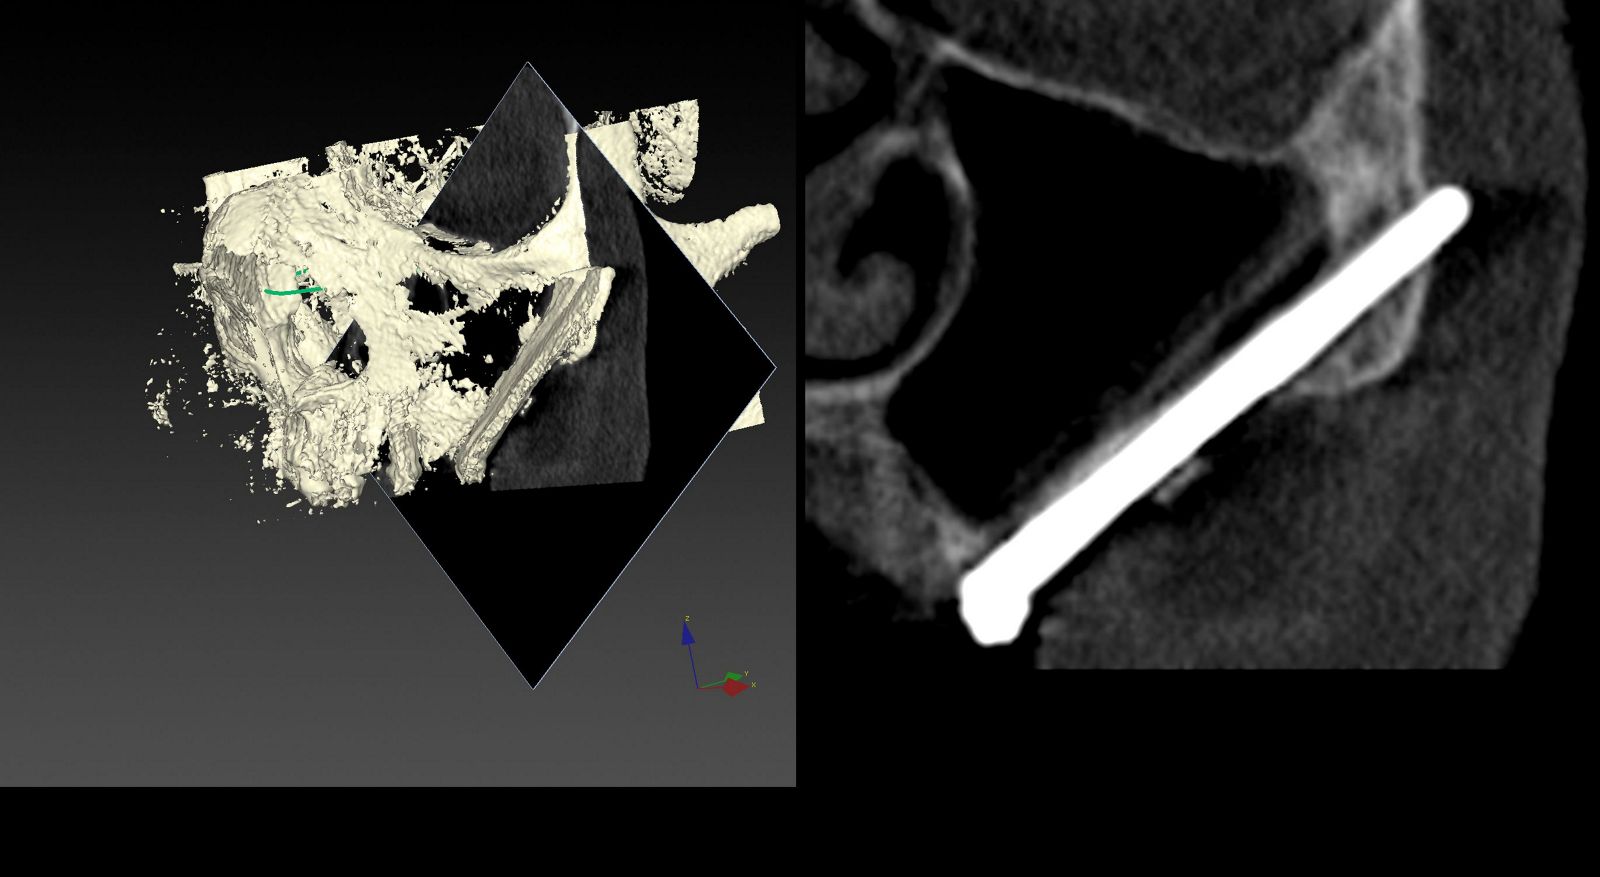

Планування операції